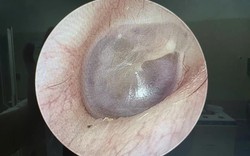

• Nam sinh trung học sốt 5 ngày rồi tử vong, bác sĩ cảnh báo: Bệnh phổ biến nhưng không thể xem nhẹ

Nam sinh trung học sốt 5 ngày rồi tử vong, bác sĩ cảnh báo: Bệnh phổ biến nhưng không thể xem nhẹ

Nam sinh xuất hiện sốt và nhiều biểu hiện khó chịu nhưng trì hoãn điều trị suốt 5 ngày. Khi được gia đình đưa vào khoa cấp cứu, em đã trong tình trạng kiệt sức toàn thân. Kết quả kiểm tra khiến bác sĩ không khỏi bàng hoàng.